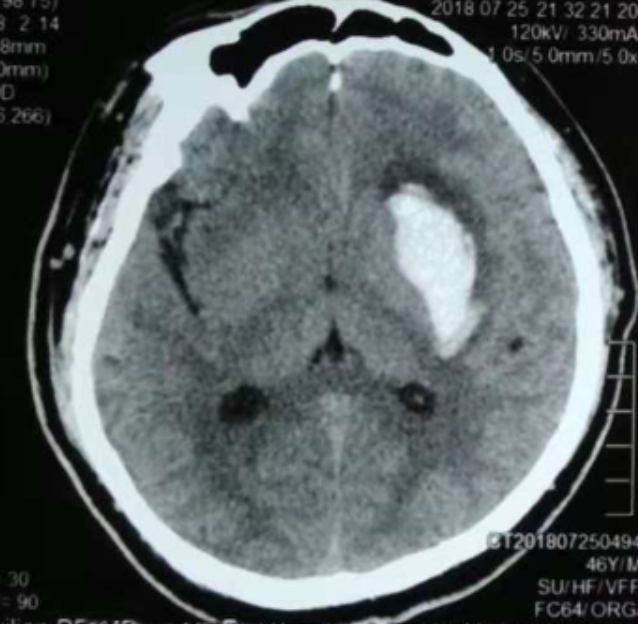

3個月前CT:腦出血

術(shù)前CT:血腫已經(jīng)液化,但仍有占位效應(yīng)